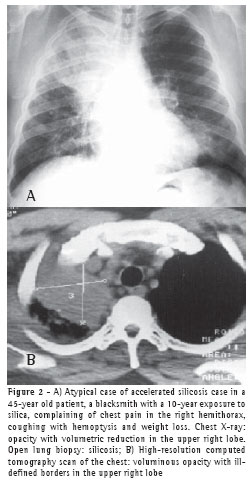

RESULTS

All 75 patients with accelerated silicosis were male. The mean age was 43 years (range, 28-76 years). The mean duration of exposure was 14.2 years (range, 7 months-38 years). Of the 75 patients, 62 (82.6%) were sandblasters, 11 (14.6%) were blacksmiths, 1 (1.4%) was a welder, and 1 (1.4%) was a metal polisher. In reference to concomitant tuberculosis, 39 patients reported a history of pulmonary tuberculosis (52%). Of those, 37 developed the disease during their exposure to silica.The diagnosis was confirmed in 31 cases: 24 through direct sputum smear microscopy; 3 through direct mycobacteria culture of the sputum; 1 through mycobacteria culture of the bronchoalveolar lavage fluid; and 3 through histopathology. In 8 patients, there was clinical and radiological suspicion of tuberculosis based on a response to specific treatment. The radiological classification of the large opacities seen on the chest X-rays was as follows: Type A in 23 patients (30.7%); Type B in 25 (33.3%); and Type C in 27 (36%) (Figures 1A and 1B). Of the cases analyzed, 74 presented bilateral conglomerate masses, whereas only 1 presented unilateral lesion (Figures 2A and 2B).

The chest X-rays of more than half of the accelerated silicosis patients showed large type B or C opacities, denoting the seriousness of the disease in these patients.

Of the 75 cases analyzed, only 1 presented a large unilateral opacity

mimicking a tumor. The diagnosis of silicosis was made via thoracotomy with open lung biopsy. Isolated PMF lesions are frequently mistaken for lung cancer. Given the higher incidence of lung cancer in these patients, it is important to take a diagnostic approach in order to effectively differentiate malignant pneumoconiosis lesions from benign ones.(19)